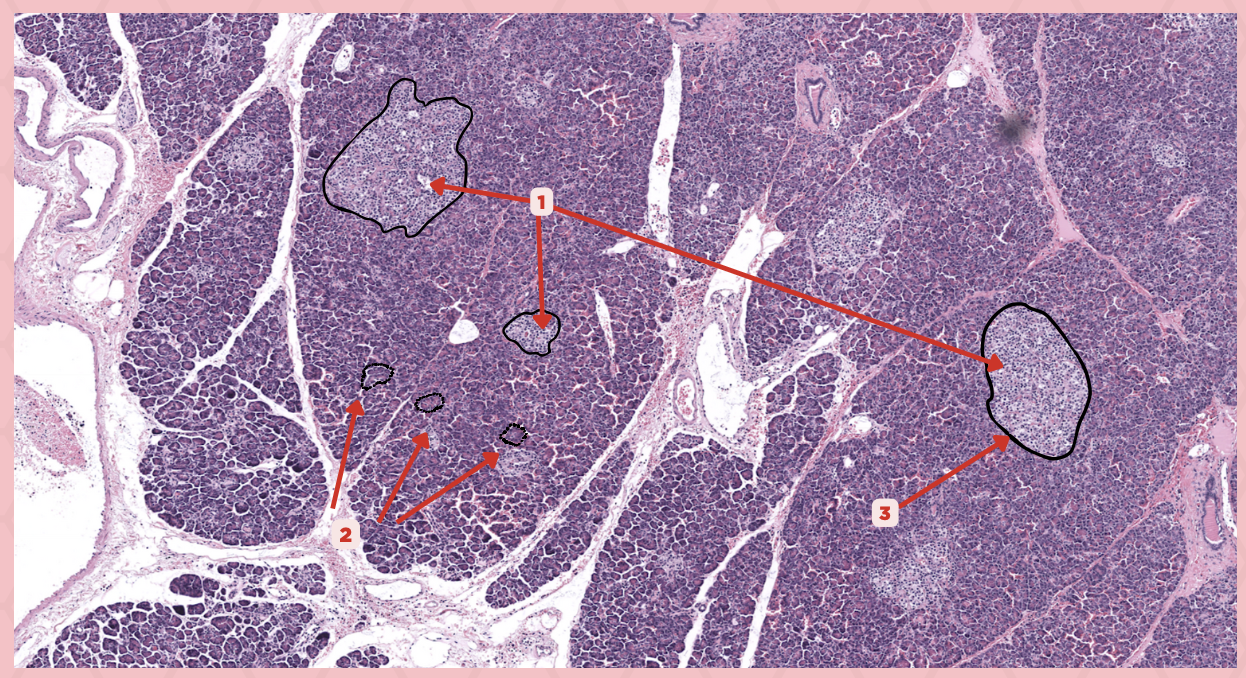

Pancreas

Identify the specimen.

Islets of Langerhans

Identify the structure labeled as 1.

Pancreatic Acini

Identify the structure labeled as 2.

Reticular Tissue

Identify the structure labeled as 3.

Beta-cells

Which cells occupy the central area of #1?

Pancreatic Acini

#3 delineates the pale- staining cells from the darker-staining cells. What do you call the darker-staining cells?